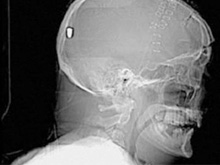

Фото новостиВ Британии у пациента, который поступил в клинику с подозрением на инсульт, врачи обнаружили пулю в голове. Но остается неизвестным, как мужчина получил ранение.

Рентгеновские снимки головы показали, что в полости черепа находится инородный предмет. Мужчине сделали томографию головы, и врачи установили, что этим предметом является пуля.

Эксперты по баллистике, изучив снимки пациента, пришли к выводу, что пуля, застрявшая в затылочной области, могла попасть туда через глаз. Но мужчина не помнит, что именно с ним произошло.